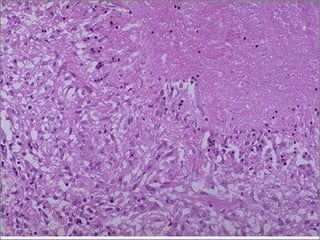

Caseous Necrosis

• Gross: Resembles cheese

• Micro: Amorphous, granular eosinophilc

material surrounded by a rim of

inflammatory cells

– No visible cell outlines – tissue architecture

is obliterated

• Usually seen in infections (esp.

mycobacterial and fungal infections)

Caseous necrosis -- micro

Caseous Necrosis • Gross:Resembles cheese • Micro: Amorphous, granular eosinophilc material surrounded by a rim of inflammatory cells – No visible cell outlines – tissue architecture is obliterated • Usually seen in infections (esp. mycobacterial and fungal infections)